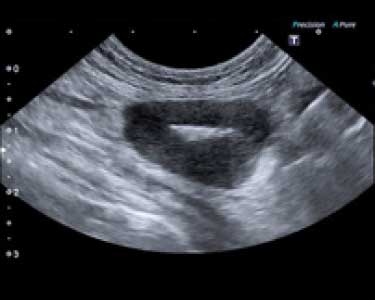

リンパ節転移の超音波写真